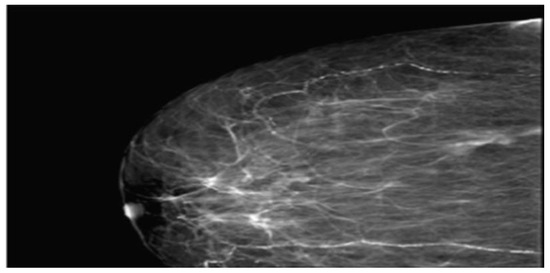

The pathological result identified macroscopically a tumor mass of 1.5x1.2 cm, situated 1 cm below the skin, 1.5 cm from the deep resection margin, and 9 cm, 7 cm, 8.5 cm, and 6 cm from the other resection margins. Multiple fragments measuring 5.5x5.2 cm in size, composed of adipose tissue containing lymph nodes, were also observed. The histopathological appearance corresponded to an invasive mixed mammary carcinoma – 70% mucinous carcinoma and non-specific invasive ductal carcinoma (Figure 4 and Figure 5), Nottingham grade II %E% (architectural grade = 3, nu-clear grade = 2, mitotic grade = 1), and tumor staging pT1cN0Mx. The diagnosis of mucinous carcinoma was based on histological characteristics, namely nests and groups of tumor cells forming within a mass of extracellular mucin.

Figure 4. Microphotograph smear examination showing invasive ductal carcinoma component.

Figure 5. Microphotograph smear from case has identified mixed (ductal and mucinous) carcinoma.

The NOS type ductal carcinoma component consists of nests and trabeculae of varying sizes arranged in a moderately connective stroma; the tumor cells are polygonal, slightly larger than those in the mucinous component, with no distinct cell boundaries, moderately eosinophilic cytoplasm, and euchromatic or vesicular nuclei, with small nucleoli (HE10X).

The mucinous carcinoma component is made up of medium-sized polygonal cells, with poorly and focally visible cell borders, with eosinophilic or pale cytoplasm, with clear intracytoplasmic vacuoles and a small euchrome nucleus, and some have the appearance of signet ring cells (HE20X).